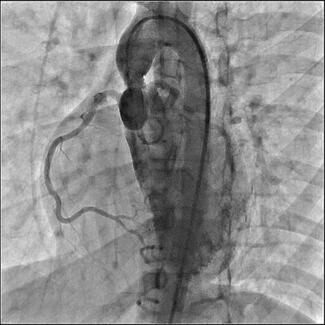

A 72-year-old gentleman presented with angina. He had previously undergone percutaneous coronary intervention (PCI) to the right coronary artery and left circumflex artery (LCX) with drug-eluting stents. Coronary angiography revealed a long segment of moderate stenosis in the proximal to mid left anterior descending artery (LAD) (Figure 1A). This was treated with Absorb bioresorbable vascular scaffolds (BVS; Abbott Vascular) (Figure 1B) with the use of intravascular ultrasound to confirm adequate stent expansion. He represented 5 years after his PCI with atypical symptoms. A computed tomography coronary angiogram showed the BVS were no longer visible and only the platinum markers were seen (Figure 1C). The scaffolds had been completely reabsorbed, allowing the use of non-invasive imaging to obtain high-quality diagnostic images not affected by artefact, as seen with the DES in the LCX (Figure 1D) preventing the vessel being assessed with the same clarity.